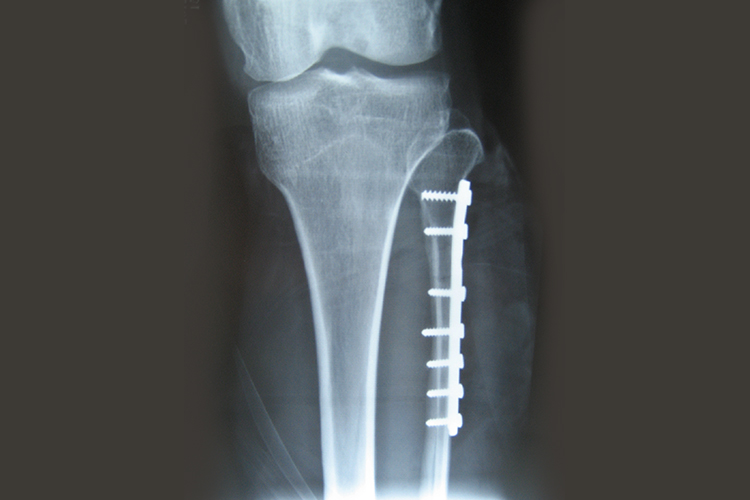

腓骨骨折

腓骨骨折打钢钉,若骨折线呈斜形,可用拉力螺丝钉由前向后打入骨折部位,使骨片间产生压缩力,螺丝钉的长度必须能钉穿后侧皮质,但不要向外伸出太多以致影响腓骨肌腱鞘。如果为横行骨折或远侧骨片较小,可纵行分开跟腓韧带纤维,显露外踝尖端,打入长钢钉,也可用其他形式的髓内钉经过骨折线打入近侧骨片髓腔中。